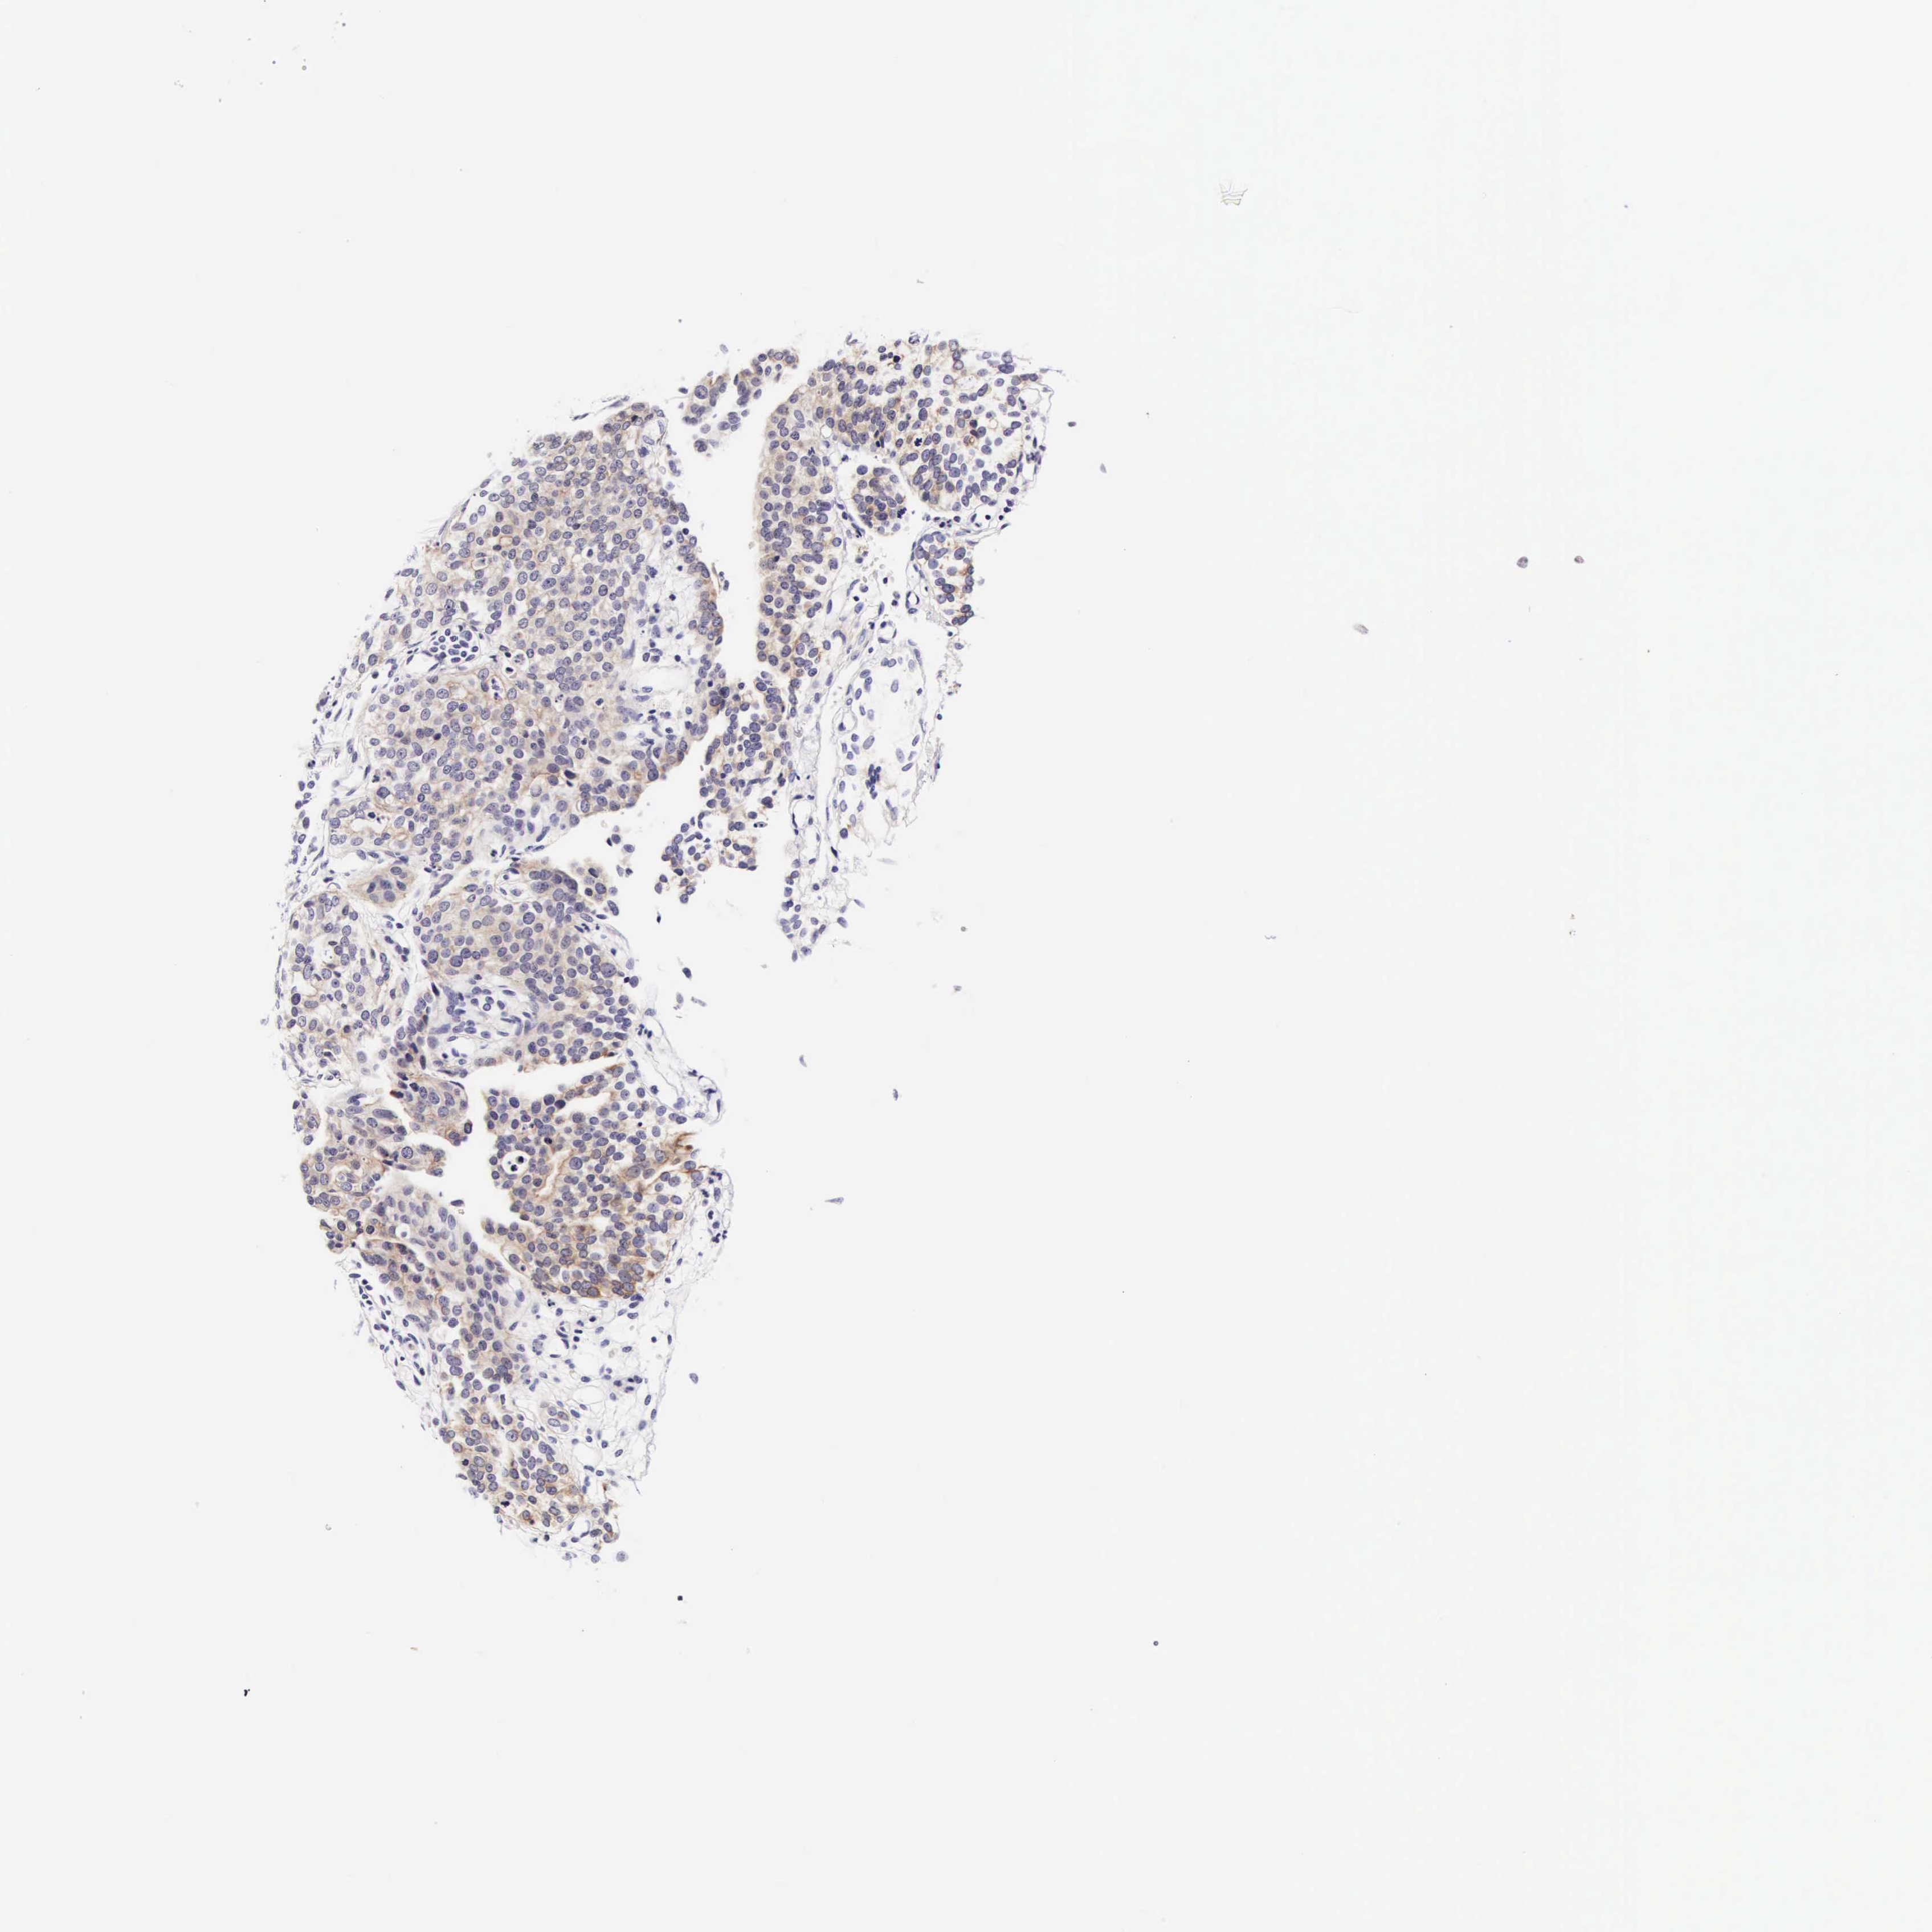

UROTHELIAL CANCER - Protein expressioni

A mouse-over function shows sample information and annotation data. Click on an image to view it in a full screen mode. Samples can be filtered based on level of antibody staining by selecting one or several of the following categories: high, medium, low and not detected. The assay and annotation is described here.

Note that samples used for immunohistochemistry by the Human Protein Atlas do not correspond to samples in the TCGA dataset.

Antibody stainingi

Antibody staining in the annotated cell types in the current human tissue is reported as not detected, low, medium, or high, based on conventional immunohistochemistry profiling in selected tissues. This score is based on the combination of the staining intensity and fraction of stained cells.

Each image is clickable and will lead to virtual microscopy that enables deeper exploration of all samples and also displays staining intensity scores, fraction scores and subcellular localization as well as patient and tissue information for each sample.

Antibody HPA000647

Staining

High

Medium

Low

Not detected

Intensity

Strong

Moderate

Weak

Negative

Quantity

>75%

75%-25%

<25%

None

Location

Nuclear

Cytoplasmic/membranous

Cytoplasmic/membranous,nuclear

Urothelial carcinoma, High grade

Urothelial carcinoma, Low grade